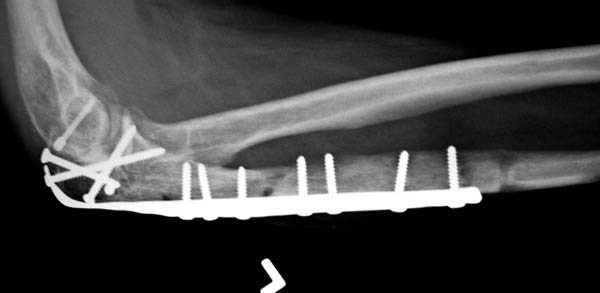

Для фиксации перелома локтевого отростка на сегодня множество преконтурных с блокирующими возможностями пластин.

Стабильную фиксацию, особенно при оскольчатых

переломах, можно добиться, применяя технику Bridge Plate, и за счет тех пластин, где имеется возможность проведения множественных шурупов (2.7 мм) проксимально.

Здесь выставлены несколько случаев и варианты фиксации локтевого отростка, некоторые в комбинации с другими переломами.

1 вариант применен ACUMED локинг пластина

2 вариант

перелом локтевого отростка с переломом головки лучевой кости (использованы 2 мм шурупы)

3 вариант

перелом с capitelum humerus и проксимальной трети улна